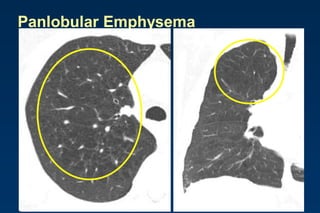

Panlobular Emphysema

Affects the whole secondary lobule

Lower lobe predominance

In alpha-1-antitrypsin deficiency, but

also seen in smokers with advanced

emphysema

Affects the entire secondary pulmonary lobule

and is more pronounced in the lower zones

Complete destruction of the entire pulmonary

lobule.

Results in an overall decrease in lung

attenuation and a reduction in size of

pulmonary vessels